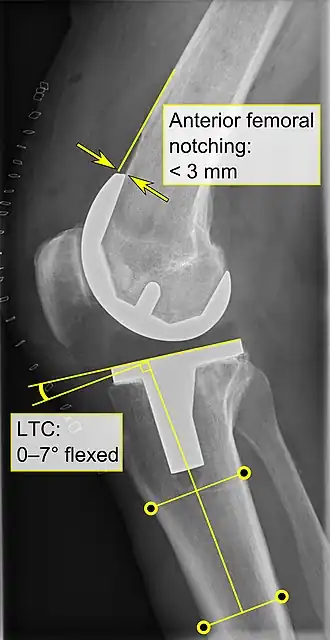

Knee replacement is routinely evaluated by X-ray, including the following measures:

- Anterior femoral notching (the femoral component causing reduced thickness of the distal femur anteriorly), seems to cause an increased risk of fractures when exceeding about 3 mm.[64]

- LTC: lateral (or sagittal) tibial component angle, which is ideally positioned so that the tibia is 0–7° flexed compared to at a right angle with the tibial plate.[63]